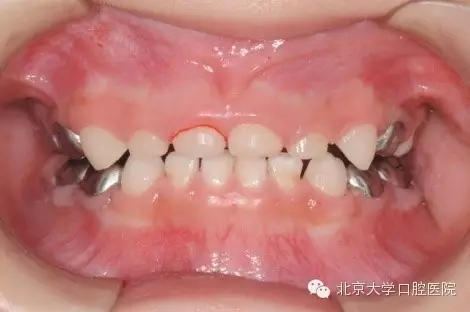

7為什么孩子的牙做了牙套?

全麻治療中醫(yī)生對缺損較大的后牙經(jīng)常會采用“預(yù)成冠”修復(fù)的方法,預(yù)成冠由不銹鋼制成,可以很好的恢復(fù)牙齒的外形并預(yù)防牙齒及充填體折斷,并不影響牙齒替換。

5.webp.jpg